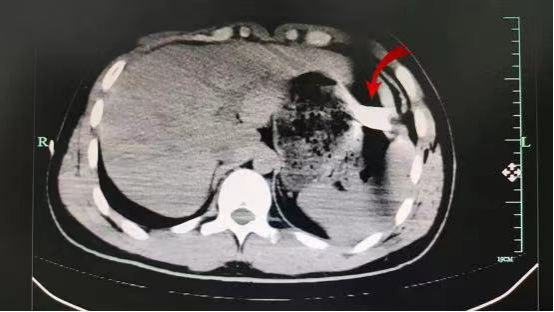

CT可见水果刀在位

患者送至手术室后,术中探查发现患者存在创伤性肝破裂、腹腔积液、肺破裂、膈肌破裂、血气胸,属于胸腹联合伤(胸腹联合伤伤情严重而复杂,危险性较大,其休克发生率高达60%,死亡率高达25%~35%),团队医生即行胸腔镜探查+膈肌修补,手术过程顺利,术后患者转ICU。